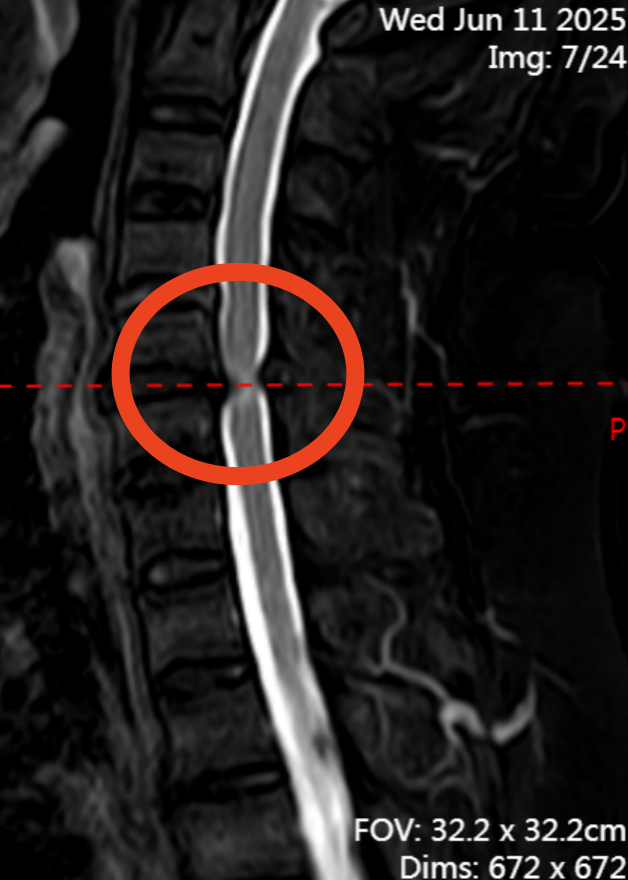

无独有偶,77 岁的潘爷爷(化姓)因双下肢无力、行走如踩棉花般不稳的症状持续 1 年,严重影响日常生活。来我院就诊,经诊断他患上了颈椎椎管狭窄症合并后纵韧带骨化症。

科室为他施行颈椎后路单开门椎管扩大成形术(C3-7),术后复查颈椎 MR 显示受压脊髓获得充分减压。潘爷爷恢复良好,佩戴支具后便能自主活动,上下楼梯、日常起居已无大碍。